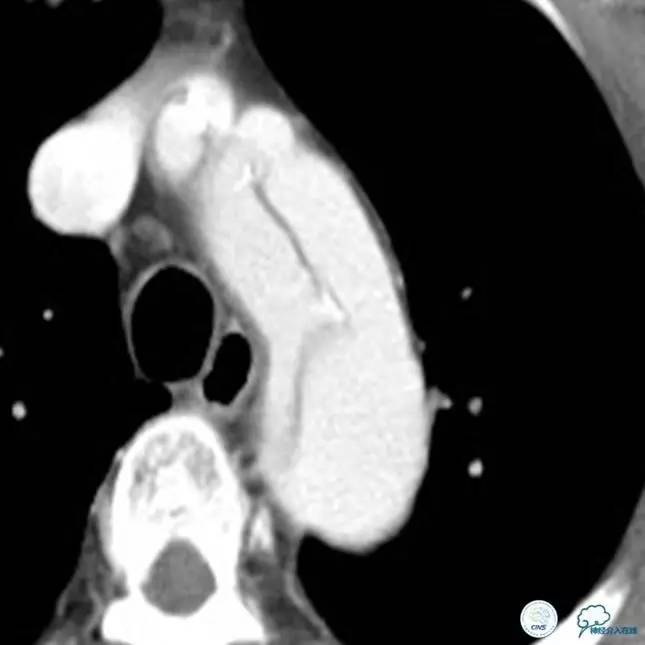

▼主动脉全程CT

诊断:

主动脉夹层 DeBakey Ⅰ型

短暂性脑缺血发作

急性心肌缺血

急性肾功能不全

急性肠系膜动脉缺血

中间诊断:

主动脉夹层 De Bakey Ⅰ型